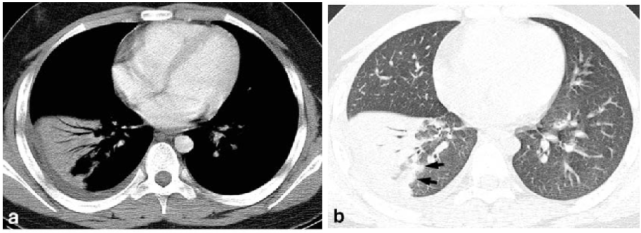

胸部 CT 提示右肺下叶背段及基底段、左肺下叶后基底段炎症(图 2)。

图 2 胸部 CT

辅助检查:CRP 97 mg/L,SAA >200 mg/L,PCT 0.26ug/L;血常规:WBC 4.0 g/L、NEU 2.50 g/L、NEU% 62.3%、RBC 5.41T/L、HGB 146 g/L、PLT 185 G/L、;肺炎支原体 IgG、IgM 抗体(颗粒凝集试验 PA 法)阴性;胸部 CT 提示右肺上叶多发斑片状、片状模糊影,边界不清,病变支气管壁增厚,部分可见支气管充气征(图 4)。

图 4 胸部 CT